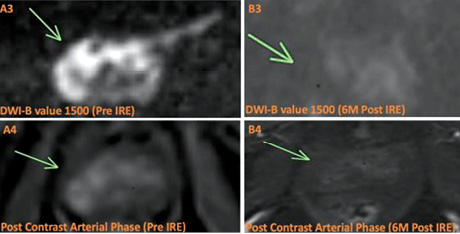

У групі первинного лікування середній рівень простато­специфічного антигену (ПСА) через 6 міс після лікування становив 3,4 нг/мл (0,8–16,3) порівняно із середнім показником до лікування 5,6 нг/мл (1,5–25), що свідчить про зниження на 39%. При контрольній мультипараметричній МРТ (мпМРТ) (рис. 2) через 6 міс після лікування у 84% пацієнтів (25/38) не було ознак хвороби при порівнянні результатів мпМРТ (Prostate Imaging Reporting and Data System — PI-RADS) = 2, тоді як у 12% виявлено нові підозрілі вогнища ураження поза межами зони абляції (PI-RADS >3), а у 4% зберігалося ураження в межах зони абляції. Контроль промежинної біопсії проведено через 1 рік після лікування (раніше, якщо на МРТ були ознаки залишкової хвороби) 13 пацієнтам. У 69% не виявлено ознак захворювання, у 31% (N-4) діагностовано клінічно значущий рак передміхурової залози за межами зон абляції (ISUP >2), клінічно значущих уражень у межах зони абляції не зафіксовано у жодного хворого. Загалом впродовж 1 року після лікування 2 пацієнти пройшли повторну НОЕ, а 1 — радикальну простатектомію, отже, 97% пацієнтів перебували під активним спостереженням. Через 2 роки із 13 пацієнтів двом проведено радикальну простатектомію, 4 пройшли повторну НОЕ і загалом 84% (11/13) залишалися під АС.

Рис. 2. МРТ передміхурової залози до та після лікування за допомогою НОЕ. Пацієнт віком 75 років із нещодавно діагностованою злоякісною пухлиною, ISUP 2, у периферійній зоні (PZ) справа, що охоплює верхівку та середню частину цієї залози. (a) МРТ до лікування. У PZ на Т2-WI видно низьку інтенсивність сигналу (стрілка) (a1), що відповідає обмеженому низькому сигналу ADC (a2) та високому сигналу на DWI (a3). Це корелювало з артеріальним підсиленням (a4). (b) МРТ через 6 міс після лікування. Відмічається підвищення низького сигналу на Т2-WI у зоні лікування, що є наслідком очікуваної атрофії (b1), з неоднорідним сигналом на ADC (b2) та відсутністю обмеження на DWI (b3). Крім того, підсилення більше не виявляється (b4) [цит. за 2]

Примітки: ISUP — ступінь агресивності раку передміхурової залози за класифікацією Міжнародного товариства урологічної патології (International Society of Urological Pathology); Т2-WI — Т2-зважені зображення; DWI — дифузійно-зважені зображення.